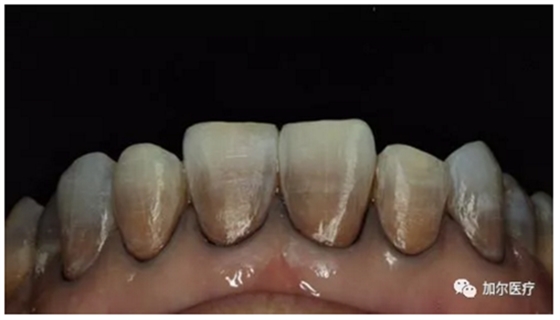

蛀牙連一半的牙冠都沒了,但是牙齒又不疼,而且還有些發(fā)黑,牙醫(yī)拍片檢查后才知道得做根管治療,那時牙痛真要人命,可是怎么判斷牙髓壞死?

簡單來說,可以看牙齒表象!觀察顏色是否變黑變暗,實際上這顆牙齒和死牙沒什么區(qū)別,不過比任何假牙好太多了,牙冠再怎么殘缺是一回事,關(guān)鍵自帶天然牙根,只要修復(fù)好和真牙咀嚼功能還是一樣,要不然怎能讓你輕易拔牙呢?

所以牙齒被蛀掉了一半,觀察牙髓壞死并不復(fù)雜,第一看患牙顏色變化,第二感知牙齒反應(yīng),重要的是一旦有慢性牙髓炎引起牙齒隱痛現(xiàn)象,一定及時到正規(guī)醫(yī)院治療,拖得越晚甚至還會引起根尖周炎。